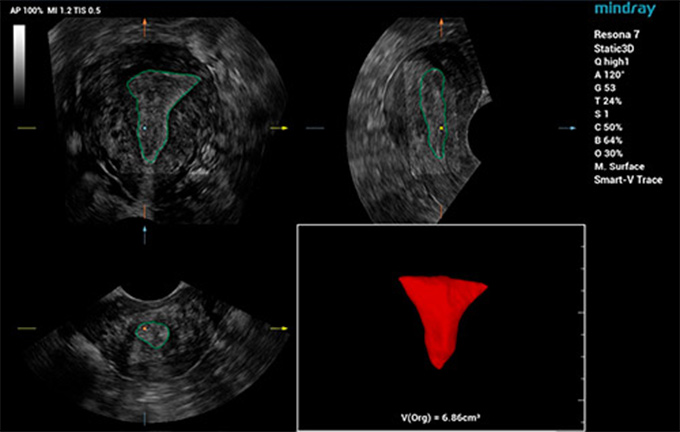

Smart ERA

A fin de mejorar la eficiencia y precisiĆ³n del diagnĆ³stico ginecolĆ³gico por ecografĆa y hacer que el diagnĆ³stico temprano de trastornos reproductivos y tumores sea mĆ”s accesible, Mindray ha desarrollado una serie de soluciones inteligentes para exĆ”menes de ecografĆa uterinos y foliculares para ayudar a los mĆ©dicos a realizar un diagnĆ³stico clĆnico eficiente. En respuesta a las necesidades de la prueba de receptividad endometrial, Smart ERA, la primera herramienta de anĆ”lisis de la receptividad endometrial completamente automatizada de la industria, desarrollada por nosotros, permite obtener imĆ”genes endometriales automĆ”ticas en 3D incluso en diferentes tipos de estructuras. Admite la mediciĆ³n automĆ”tica del volumen y el grosor del endometrio, asĆ como del Ćndice de flujo sanguĆneo endometrial. El proceso de uso simplificado mejora significativamente la consistencia del examen y la eficiencia del diagnĆ³stico, lo que permite a los ecografistas gestionar la evaluaciĆ³n previa al embarazo con mĆ”s confianza y facilidad.

Smart Pelvic

Para ayudar a los ecografistas a obtener rĆ”pidamente secciones y medidas estandarizadas en exĆ”menes complejos del piso pĆ©lvico y mejorar la eficiencia del diagnĆ³stico, Mindray ha desarrollado Smart Pelvic, una soluciĆ³n de ecografĆa inteligente para el piso pĆ©lvico. Puede obtener automĆ”ticamente mediciones pĆ©lvicas completas y ofrecer imĆ”genes 3D automĆ”ticas del hiato del elevador, junto con medidas del diĆ”metro longitudinal, el diĆ”metro transversal, el Ć”rea del hiato del elevador y el tama?o del espacio del elevador de la uretra. Los ecografistas pueden obtener datos clĆnicos completos para una evaluaciĆ³n precisa en unas pocas interacciones simples que toman solo 1/3 del tiempo que consumen los exĆ”menes tradicionales. AdemĆ”s, Mindray ofrece tres estĆ”ndares industriales primarios que admiten diferentes tipos de sondas y posibilitan un uso estandarizado.